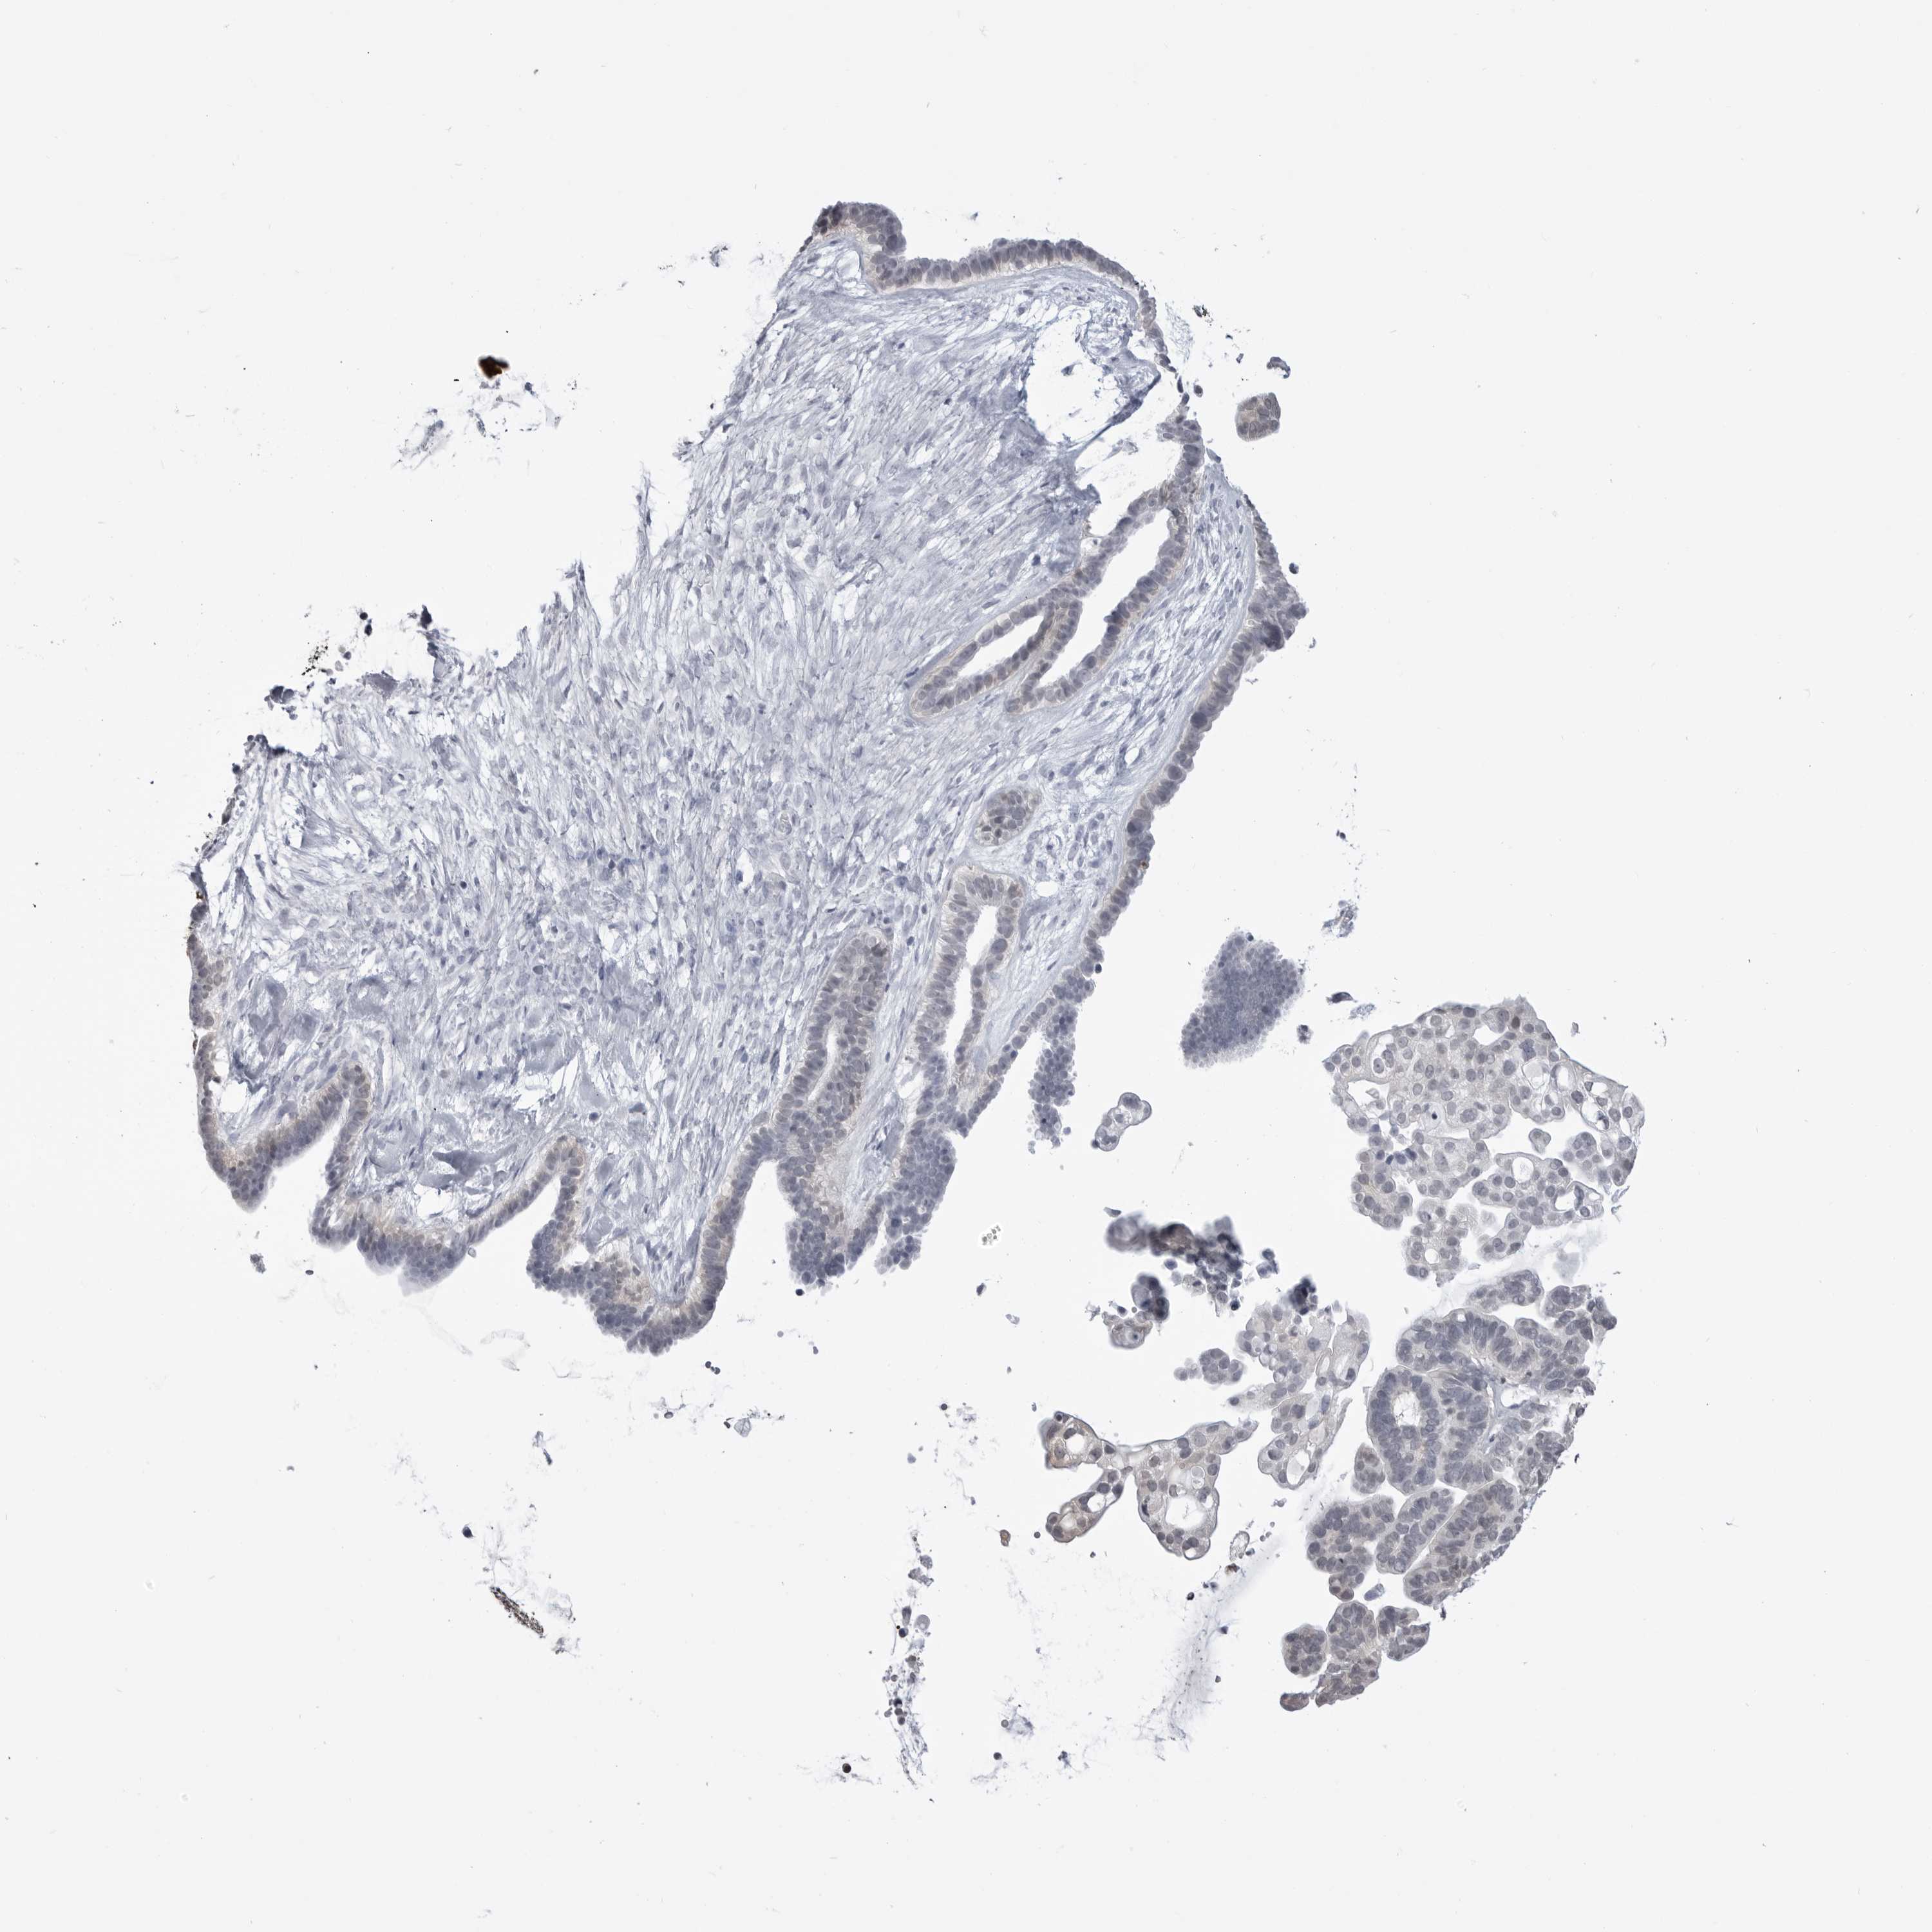

OVARIAN CANCER - Protein expressioni

A mouse-over function shows sample information and annotation data. Click on an image to view it in a full screen mode. Samples can be filtered based on level of antibody staining by selecting one or several of the following categories: high, medium, low and not detected. The assay and annotation is described here.

Note that samples used for immunohistochemistry by the Human Protein Atlas do not correspond to samples in the TCGA dataset.

Antibody stainingi

Antibody staining in the annotated cell types in the current human tissue is reported as not detected, low, medium, or high, based on conventional immunohistochemistry profiling in selected tissues. This score is based on the combination of the staining intensity and fraction of stained cells.

Each image is clickable and will lead to virtual microscopy that enables deeper exploration of all samples and also displays staining intensity scores, fraction scores and subcellular localization as well as patient and tissue information for each sample.

Antibody HPA026918

Antibody CAB013274

Antibody CAB018389

Cystadenocarcinoma, serous, NOS

Carcinoma, endometroid

Cystadenocarcinoma, mucinous, NOS

Carcinoma, NOS